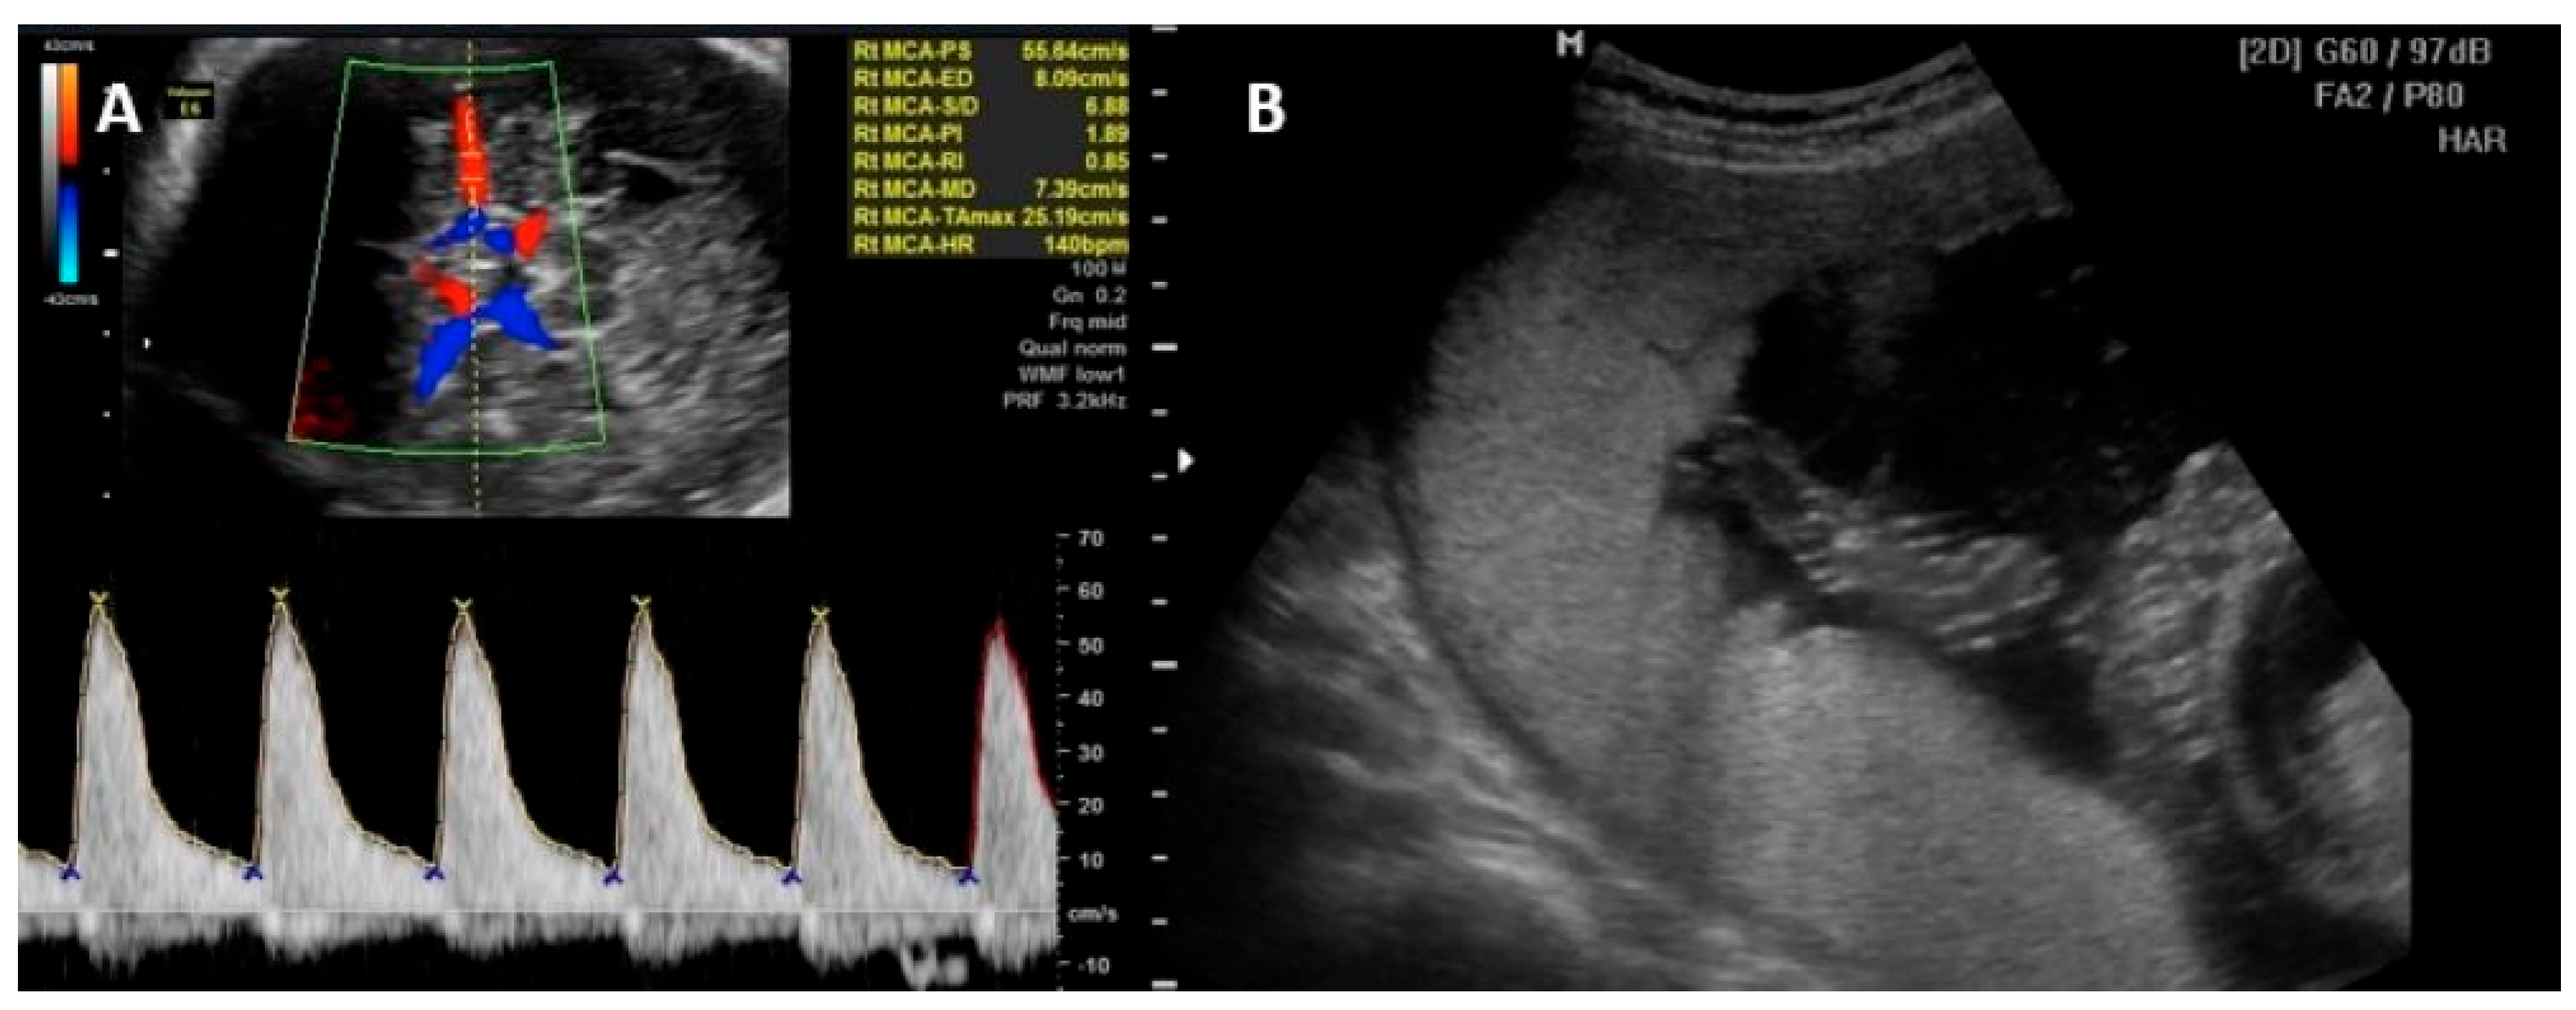

Fetal anemia is initially monitored non-invasively by assessing peak systolic velocity of the middle cerebral artery (PSV-MCA) using Doppler ultrasound. Moderate/severe fetal anemia is highly indicative of the presence of a PSV-MCA greater than 1.5 times the median (MoM) at 18 weeks of gestation or later [46,47,48,49].

Parvovirus B19 infection is unlikely the cause of fetal anemia in the absence of ultrasound changes suggestive of fetal sequelae 8 to 12 weeks after possible exposure. Cordocentesis with fetal blood sampling to determine fetal hematocrit and intrauterine transfusion may be required in cases of fetal hydrops or severe fetal anemia [46,47,48,49]. Other signs of fetal parvovirus B19 infection include fetal ascites and cardiomegaly. Generalized edema and pericardial effusion occur in more advanced stages of the disease. Hyperechogenic bowel, meconium peritonitis, increased nuchal translucency in the first trimester, and amniotic fluid abnormalities have also been reported as US anomalies [50,51,52]. Figure 2 illustrates the PVS-MCA measurement and the intrauterine transfusion.

Figure 2.

(A) Peak of systolic velocity of the middle cerebral artery Doppler measurement technique. (B) Intrauterine transfusion with the needle in the vein at level of umbilical cord insertion on placenta.

The tool used to determine the degree of anemia noninvasively, without the need for fetal blood sampling, is the PVS-MCA, which when elevated (>1.5 MoM) is highly suggestive of moderate/severe anemia. Other ultrasound parameters such as fetal skin edema, ascites, or pleural or pericardial effusions may occur and are suggestive of severe anemia, but these are also parameters found later in the fetus [39].

Due to fetal myocarditis, the degree of hydrops may not correlate with fetal hemoglobin, and fetal echocardiography is useful in these cases [42]. PSV-MCA should be used as monitoring after intrauterine transfusion for anemia and fetal complications, even though its prediction for anemia decreases [39].